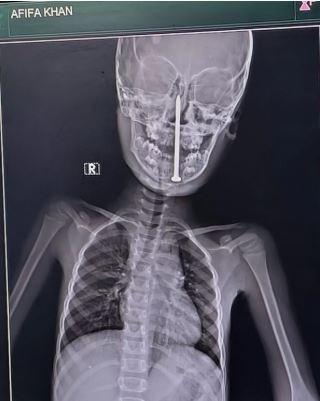

Hindistan'da 7 yaşındaki bir kız çocuğunun beynine saplanan 8 santimetrelik çivi, doktorlar tarafından başarıyla çıkarıldı. Oyun oynarken düşen küçük kızın boynunu ve çenesini delen çivi, beynine kadar ulaştı. Tomografi, çivinin hayati damarların çok yakınından geçtiğini gösterdi.

Yapılan tomografi, çivinin alt çeneden girip kafatasına kadar ilerlediğini ve hayati damarların çok yakınından geçtiğini gösterdi. Ameliyat, ertesi gün (16 Mayıs'ta) Dr. Vaibhav Jaiswal ve Dr. Sameer Mishra tarafından Lucknow'daki King George Tıp Üniversitesi Travma Merkezi'nde yapıldı.